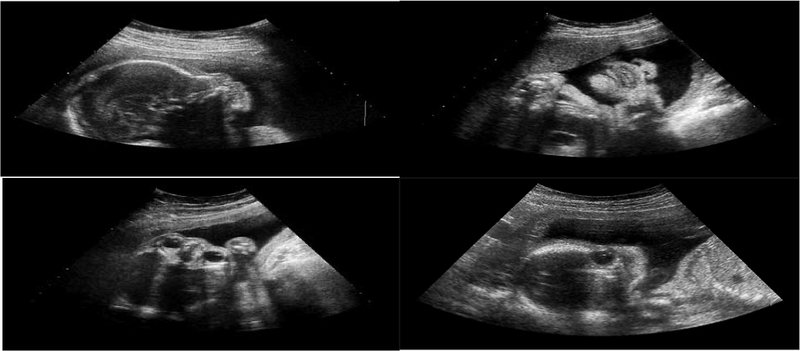

Siêu âm là một công cụ quan trọng giúp theo dõi sức khỏe của mẹ và bé trong suốt thai kỳ. Sau đây là những loại siêu âm được thực hiện để chẩn đoán tình trạng thai nghén thất bại sớm mà bạn có thể tham khảo: